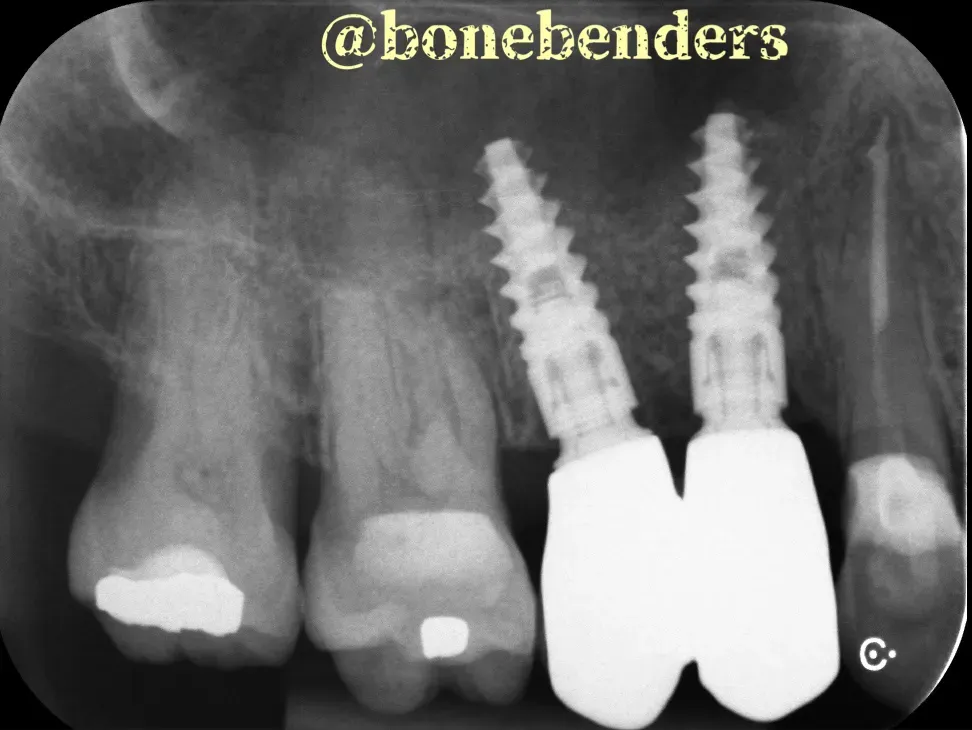

L’obiettivo della procedura qui è sostituire i denti 4 e 5 (premolari superiori destri) con impianti.

Come dimostrato dall’immagine sopra, i volumi ossei erano insufficienti per il posizionamento di impianti adeguatamente dimensionati.

Le immagini sottostanti mostrano i risultati clinici e radiografici della procedura. Gli impianti sono due Newton di Kalodon 3.8x13 mm. È chiaro che l’espansione ossea è tridimensionale e che anche il volume del tessuto cheratinizzato è notevolmente aumentato.

Pensaci: tutto questo è stato realizzato naturalmente, senza innesti. I tempi di guarigione sono identici a quelli delle procedure osteotomiche classiche. Non c’è bisogno di aspettare periodi più lunghi, cosa necessaria, al contrario, con GBR e i sollevamenti laterali del seno. È davvero sorprendente ciò che possiamo ottenere con le tecniche di “bonebending”.

Come vedi, l’osteointegrazione è perfetta e il risultato estetico eccellente. Tutto questo senza biomateriali, senza membrane, senza complicazioni. Solo la potenza della biologia naturale guidata da tecniche precise.